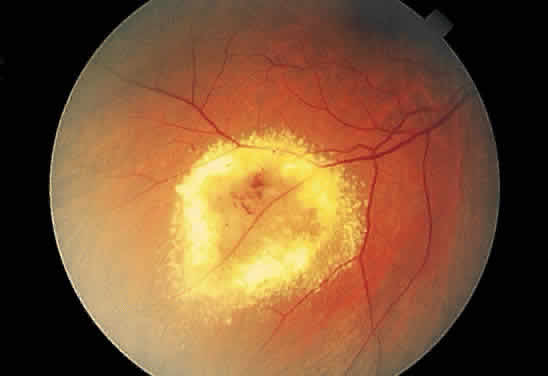

Necrotic retina has a white appearance. Necrosis may result from a variety of inflammatory conditions, including viral, fungal, and protozoal (Toxoplasma) retinitis. Each type of retinitis appears, in part, as a white retinal lesion. Cytomegalovirus retinitis (Fig. 24) resembles a pizza pie with an admixture of white (retinal inflammation) and red (hemorrhage) colors (Fig. 25). The retinal abscesses of fungal retinitis are white. Likewise, the satellite lesion of retinochoroiditis caused by active Toxoplasma (the choroidal inflammation is merely in response to the primary retinal infection) is white (Fig. 26). The white appearance of a lesion from inactive Toxoplasma results from the destruction of neurosensory retina, retinal pigment epithelium, and choroid to permit a direct view of the sclera (Fig. 27). Necrosis in retinal-derived neoplasms is white; the appearance of regressed (necrotic) retinoblastoma often is described as “cottage cheese.”10

Fig. 27. Fundus photographs of quiescent toxoplasmosis chorioretinitis scar. The white center is the result of destruction of the neurosensory retina, retinal pigment epithelium, and choroid, leaving only the sclera in view.